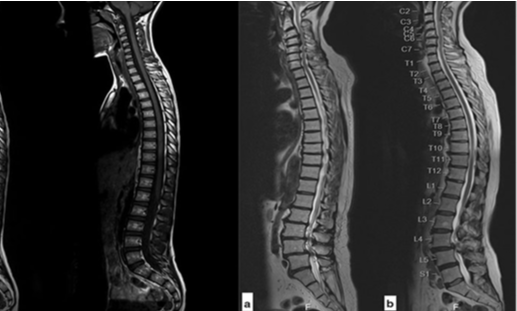

Chụp X quang cột sống là một phương pháp dùng hình ảnh để chẩn đoán rất phổ biến và quan trọng trong y học. Được sử dụng để đánh giá và chẩn đoán các vấn đề liên quan đến cột sống và các cấu trúc xương xung quanh. Phương pháp này cung cấp hình ảnh hai chiều của cột sống, cho phép bác sĩ đánh giá kích thước, hình dạng và vị trí của các đốt sống và mô mềm xung quanh. Chụp X quang cột sống thường được sử dụng để:

Dưới đây là một số bệnh có thể được chẩn đoán thông qua chụp X quang: